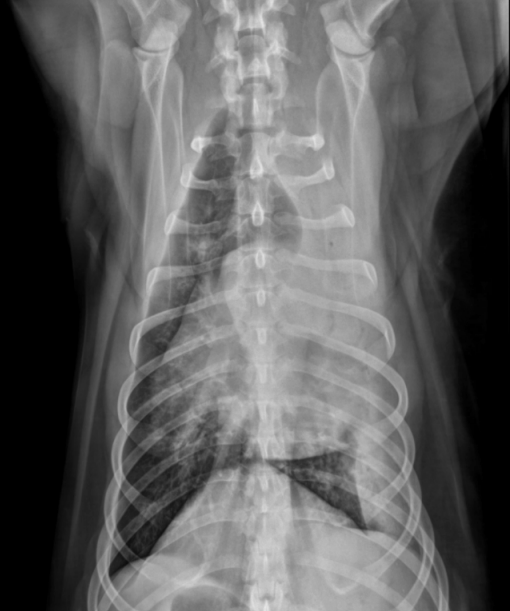

● 12 yo dog

● Coughing for 2 months

alveolar pattern caudodorsally (black tree visible)

fat in ventral thorax

cardiac silhouette lifted and rounded, maybe free fluid

on VD: mass effect